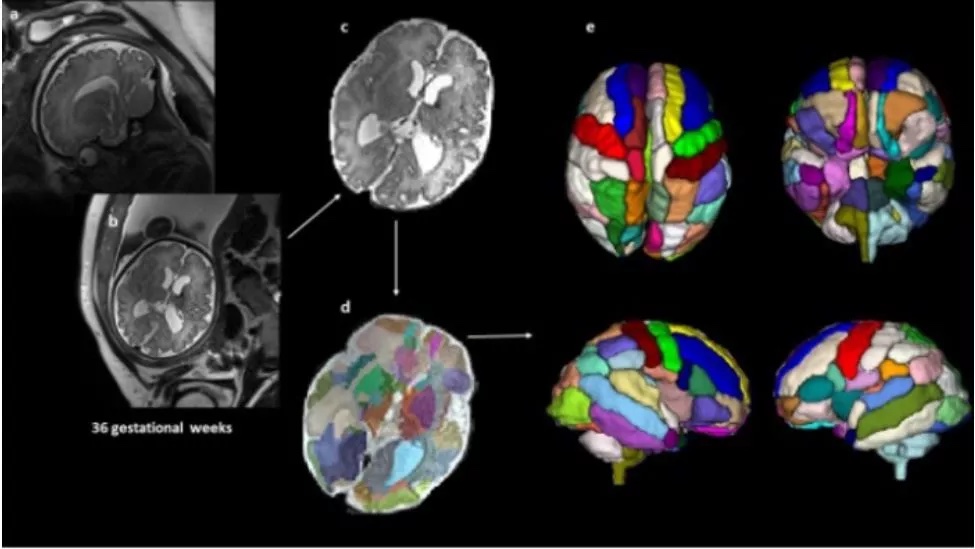

Brain differences tied to autism can be detected in the womb Live Science - April 7, 2022

Brain scans of babies in the womb may reveal whether a child is at risk for developing autism later in life, early research suggests.

A small study of 39 fetuses found that, by 25 weeks of gestation, certain brain regions looked different in the unborn babies who went on to be diagnosed with autism compared with those who were not diagnosed with the condition.